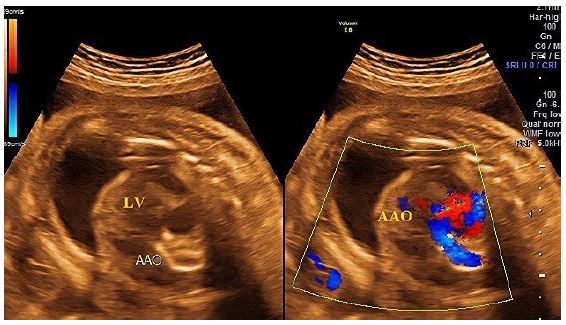

A transabdominal fetal echocardiogram performed at 27 weeks of gestation revealed an abnormal cardiac axis, ventricular asymmetry with a smaller right ventricle, and severe calcifications of the tricuspid valve, pulmonary valve, and descending aorta (Figure 1). Cardiac function was borderline, with considerable pericardial effusion and a circumferential myocardial performance index within normal limits for the left ventricle. The four-chamber view was abnormal, with atrioventricular and semilunar valve dysfunction likely secondary to progressive calcification of the great vessels (Figure 2). The fetal heart rate was 145 beats per minute in sinus rhythm.

A follow-up fetal echocardiogram at 29 weeks demonstrated diffuse echodense calcification involving the entire thoracic and abdominal aorta, the pulmonary trunk, its major branches, and lobar, segmental, and subsegmental intrapulmonary branches, as well as the visualized coronary arteries. Additionally, the tricuspid annulus and its leaflets were severely calcified with restricted movement. The mitral annulus was also calcified with thickening of the anterior leaflet. There was echogenic thickening of the apical trabecular part of the right ventricle and its moderator band, indicating ischemic changes secondary to widespread coronary calcifications.

Figure 2: Clinical image.